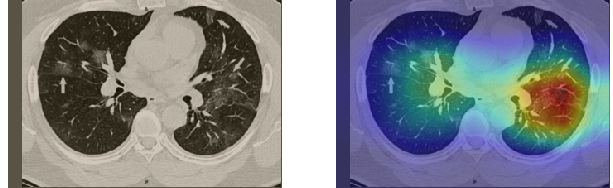

A wide variety of typical and atypical CT abnormalities have been reported for COVID-19 patients in various studies [58, 59]. So, we tested our models on external CT images extracted from these two publications as they feature typical findings of COVID-19 pneumonia marked by specialists. In order to make sure that not any of the extracted images are unintentionally included in our datasets, specifically the COVID19-CT dataset, we use the model trained on the SARS-CoV-2 dataset. First, the InceptionV3 model is employed to classify the extracted CT images. The model is able to correctly classify the given CT images as COVID-19. Second, in order to interpret the model’s generalization capabilities, we apply the Grad-CAM technique to visualize the regions of abnormalities that are considered. By assessing the different CT images in Figure 15, we can see that the model accurately localizes the disease-related regions. Even more interesting is the fact that the model ignores any specific marks in the images like letters and only localizes the COVID-19 related regions. These visual explanations show the success of our models to learn relevant, generic visual features related to COVID-19 and are capable to correctly classify CT images outside the datasets on which they are trained.

Figure 16 shows various CT scans where only one lung is visible. The CT scans are also extracted from the paper [58] and show different CT manifestations of COVID-19 pneumonia marked by red squares. The InceptionV3 model is capable to classify them correctly as COVID-19, although it is trained on CT scans where the entire lung is visible. Intriguingly, when applying Grad-CAM we can see that all regions of abnormalities are accurately localized. This also proves the potential of our model to detect COVID-19 abnormalities in CT images outside the dataset used for training.